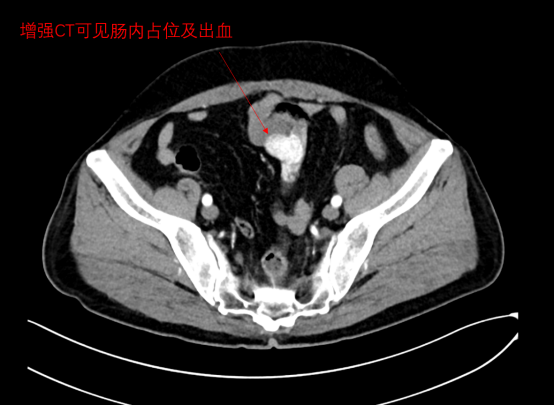

介入治疗科副主任医师肖荣紧急会诊。他快速研判患者病情,结合其肿瘤病史,敏锐地分析了最新的腹部增强CT影像,发现出血并非普通溃疡或血管畸形,而是由小肠肿瘤破裂所致。